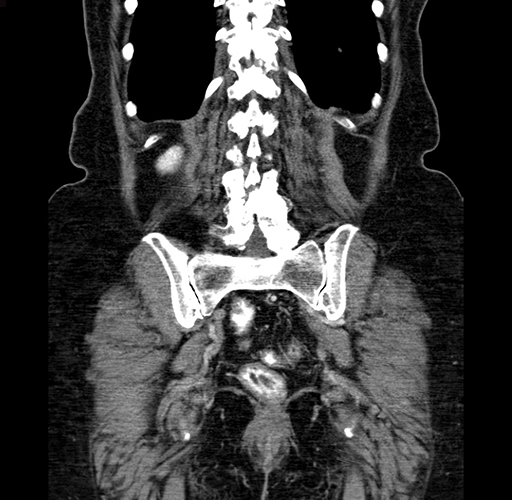

Pre-Chemo: Axial Venous

Pre-Chemo: Coronal Venous

Axial Venous

Coronal Venous

Imaging analysis

Based on your CT findings, which issue(s) would give reason for "planned slowing down moment(s)" in this case?

Considering a standard right hepatectomy procedure, what step(s) of the operation would you do differently in this case?